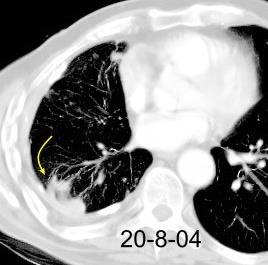

Marzo 2014: Perforación longitudinal distal secundaria a episodio de vómito (síndrome de Boerhaave). Derrame pleural izdo. que evoluciona a empiema.

Wang C-T et al. Tension hydropneumothorax in a Boerhaave syndrome patient: A case report . World J Emerg Med, 2021. Katabathina V et al. Nonvascular, nontraumatic mediastinal emergencies in adults:a comprehensive review of imaging findings. Radiographics. 2011.